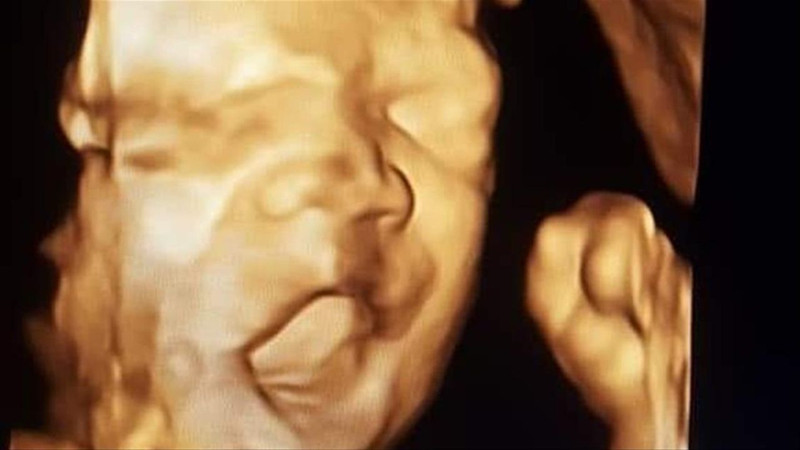

- Hamilelik sürecinde fetüs sağlığının kontrolünde de kullanılabilir.

Renkli ve normal ultrason arasındaki farkları anlamak için öncelikle her iki yöntemin de çalışma mantığını bilmek gerekir. Normal ultrason, yalnızca iki boyutlu görüntüler sunarken, renkli ultrason kanın yönü ve hızı hakkında bilgi veren renkli görüntüler üretir. Bu, özellikle damar hastalıklarının teşhisi ve izlenmesinde daha fazla detay sunma avantajı sağlar. Örneğin, karotis arterinin incelenmesi sırasında damar içi plak oluşumu veya kan akışındaki bozulmalar daha belirgin şekilde görülebilir.

Renkli Ultrasonun normal ultrasondan ayrıldığı en önemli nokta, sağladığı dinamik ve üç boyutlu bilgiler sayesinde doktorların daha isabetli ve hızlı teşhis koymasına yardımcı olmasıdır. Bu nedenle, karotis arter tıkanıklığı, derin ven trombozu ve diğer damar hastalıklarının takibi gibi durumlarda yaygın olarak kullanılmaktadır. Sunduğu detaylı bilgiler sayesinde pek çok sağlık sorununun erkenden teşhis edilmesine katkıda bulunur.